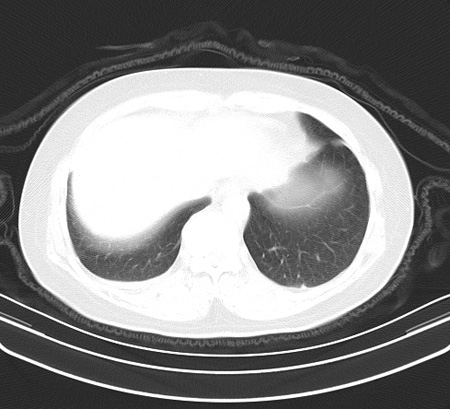

以下是引用余辉在2009-2-19 20:10:00的发言:[br]多考虑急性感染性病变,右中叶尚可见多枚小斑片状影,多为化脓性肺炎,双侧胸腔积液

以下是引用随光逐影在2009-2-19 20:33:00的发言:[br]1)考虑右肺炎症;建议抗炎治疗后复查。2)双侧胸腔积液(以右侧为甚)。

以下是引用花凤凰在2009-2-19 20:46:00的发言:[br]病人有发热,胸痛急性起病,主要病变位于右肺中叶外侧段,呈楔行改变,位于外带胸膜下,考虑为肺梗塞可能!!!!!!!!!!!!!!!!!!!!!!!!!!!!!!!!!!!